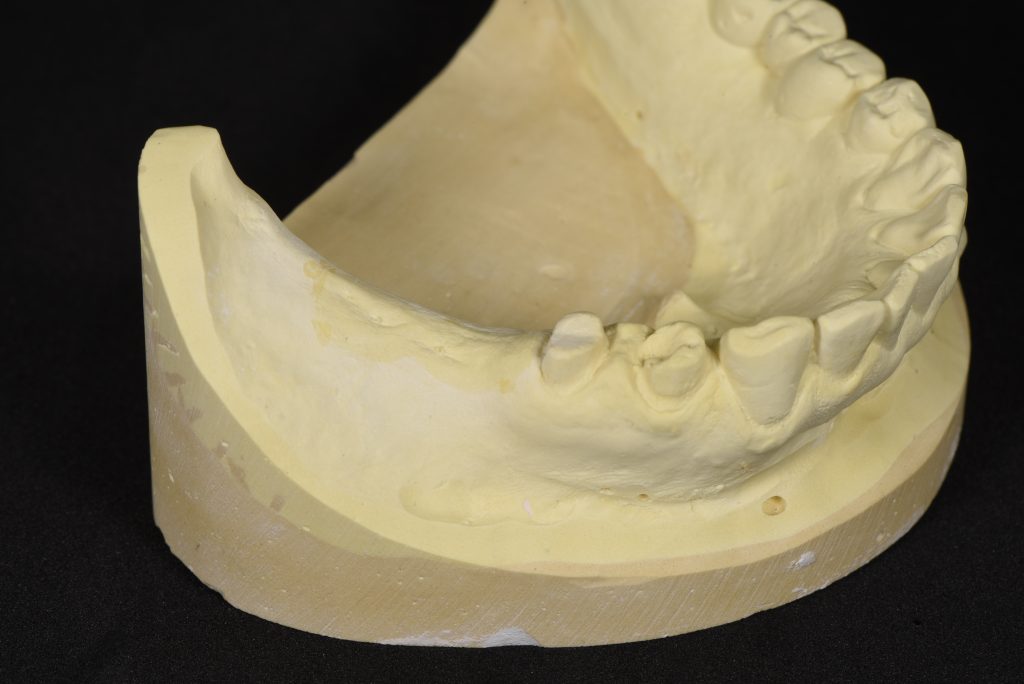

①インプラントの部分の被せ物のイメージを作成する

最終的な被せ物のイメージ